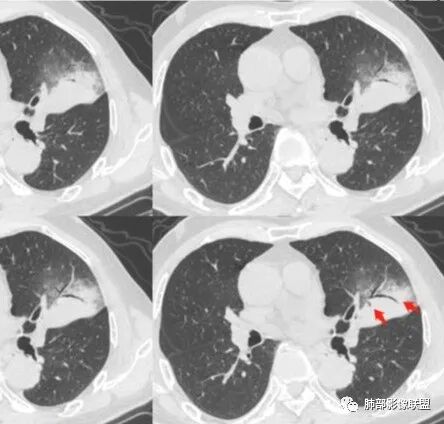

相似病例分享

肺炎型肺癌的基本影像学特点—南边老师总结

1、外周分布(起源外围由外朝内发展蔓延);

2、实变和磨玻璃阴影特点;

3、病理性支气管充气征;

4、实变内有密度较低、强化较低区;

5、“假空洞”/“蜂窝征”;

6、周围小结节,树芽征少;

7、血管造影征;

8、间质增厚改变;

9、瘤体显示;

10、淋巴结肿大;

11、胸膜改变:糊墙征;

12、前后对比进展:病灶增大、GGO区实变。